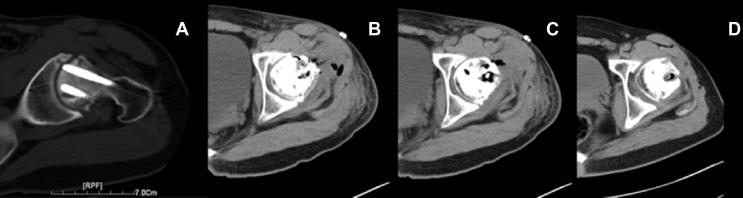

The report shows the results of the treatment of traumatic femoral head necrosis with a pedicled bone flap with pure Mg screw. A patient had avascular necrosis of the femoral head after 2 years of internal fixation of the femoral neck fracture. We removed the patient's internal fixation hollow nail, cleaned the necrotic bone tissue and took part of the same ipsilateral pedicle iliac bone graft in the femoral head defect with biodegradable pure Mg screw fixation. Within 2 years after the surgery, the patients had no significant progressive necrosis of the femoral head. Postoperative Harris scores showed that the patient's left hip function was significantly improved compared with his preoperative state. The pure Mg screw in the body had gradually degraded. After 2 years, the screw's diameter had been significantly reduced compared with 3 days after the surgery. The postoperative Harris score showed that the patient's left hip function was significantly improved compared with the second preoperative examination.